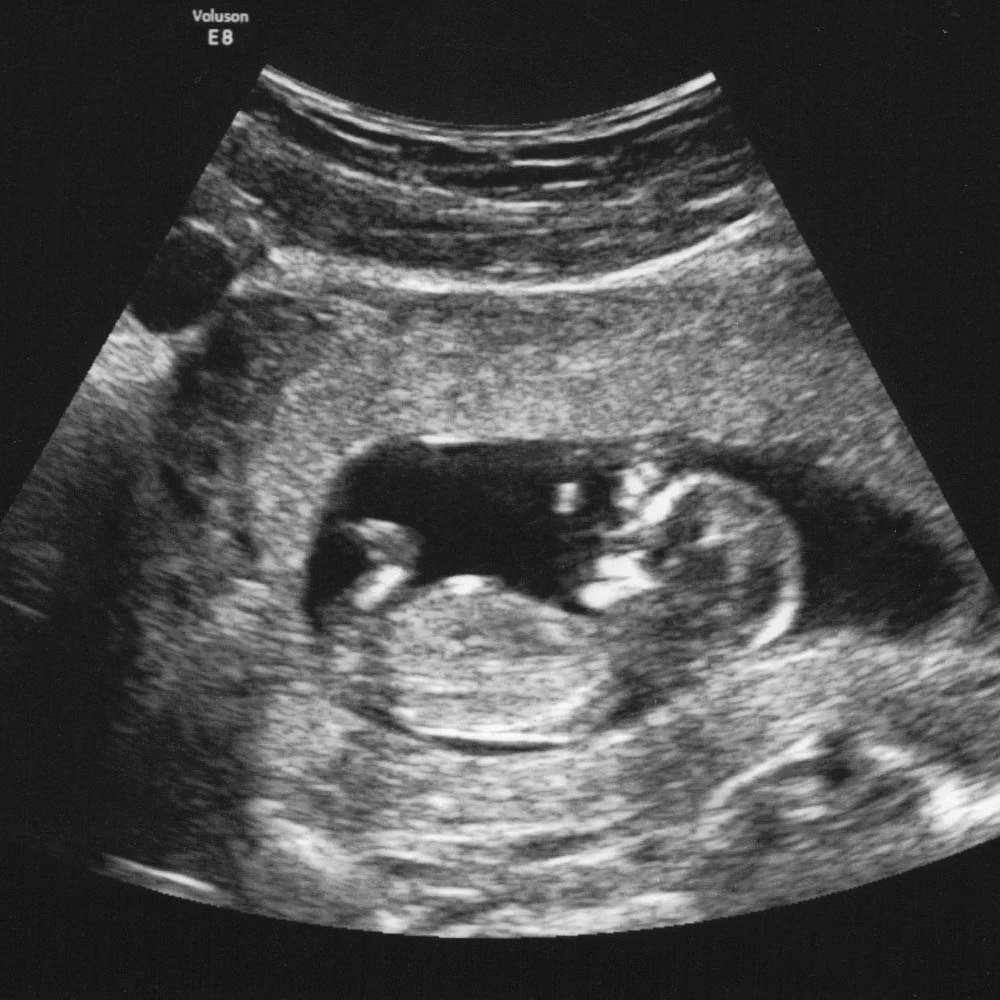

На четырнадцатой неделе при хорошем чувствительном аппарате УЗИ уже можно определить пол ребенка.